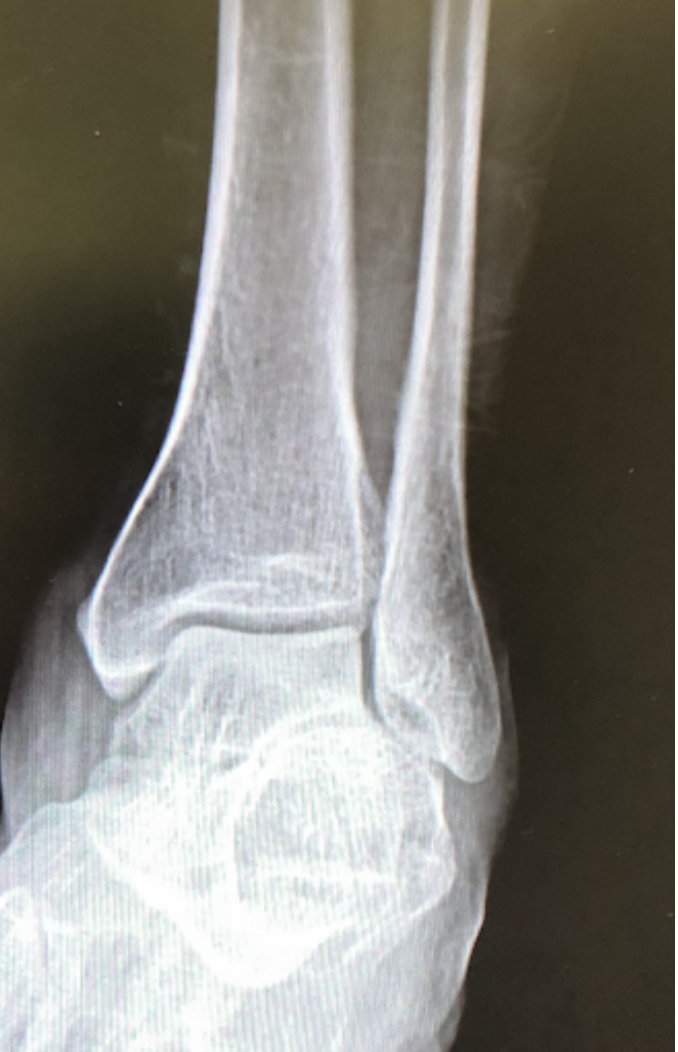

14

Q

What view is this?

A

Ankle AP